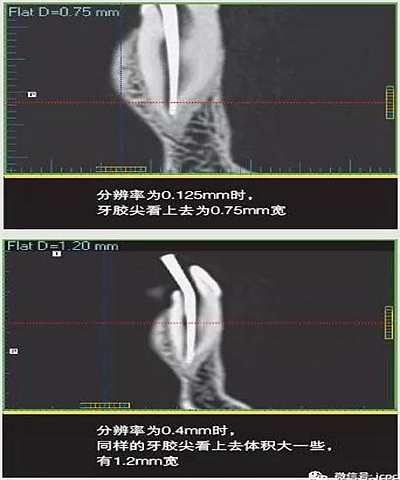

(3)部分容積效應(yīng)產(chǎn)生的偽影

如果探測(cè)器中一個(gè)高對(duì)比度物體的體積小于體素尺寸,則該對(duì)象將會(huì)有效地填充入整個(gè)體素,使其看起來(lái)比實(shí)際物體大。牙膠周邊碎片的顯影就是其中一個(gè)很好的例子,如果牙膠周邊碎片的體積小于體素大小,則圖像上會(huì)看起來(lái)比實(shí)際的大。